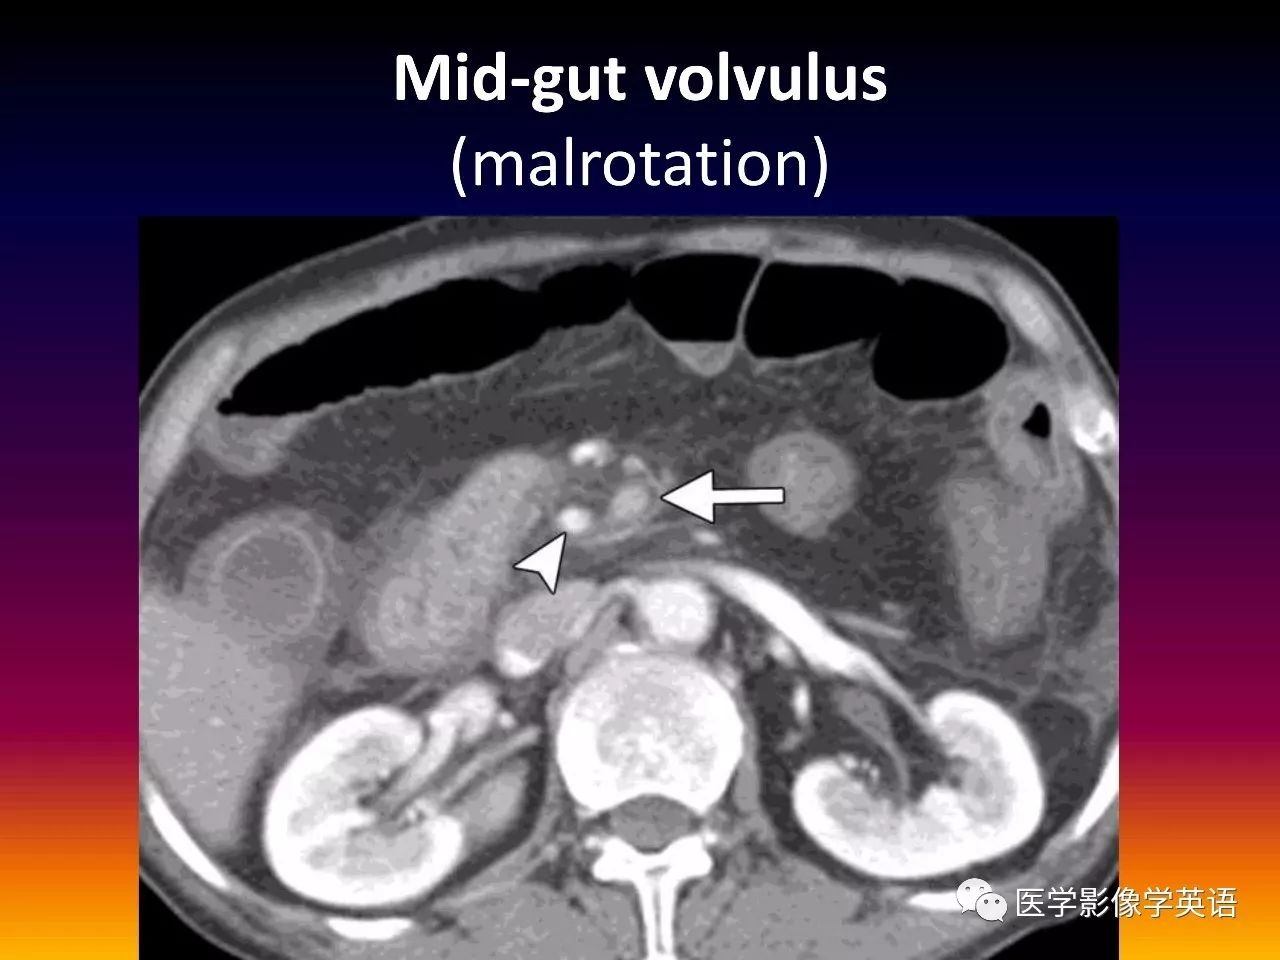

82. Mid-gut volvulus (malrotation)

83. Mid-gut volvulus (malrotation)

84. Mid-gut volvulus (swirl sign)